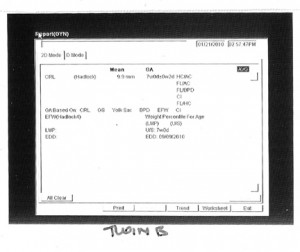

Before I go to sleep, I’ll post the first images and stats of our twins below – twin A (lower in the uterus) and twin B. Love you all!